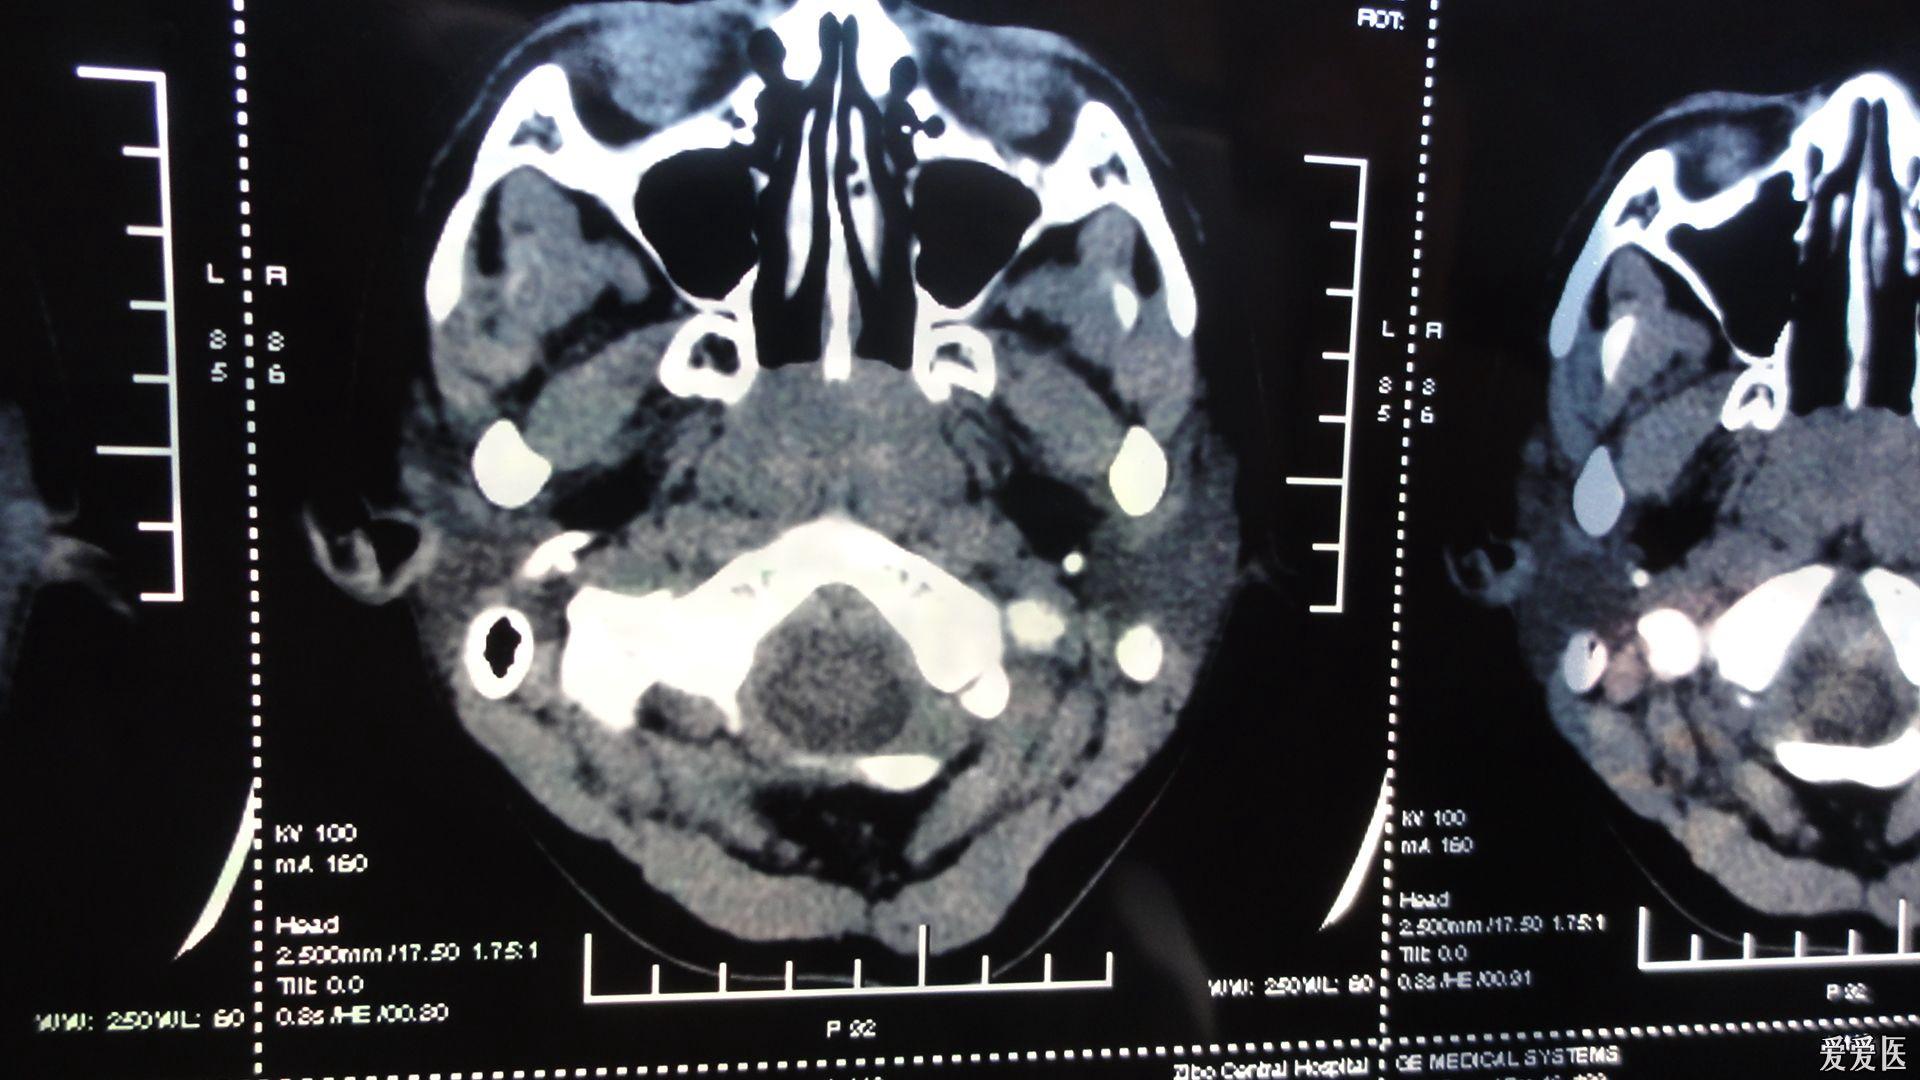

内科大夫求助增殖体肥大